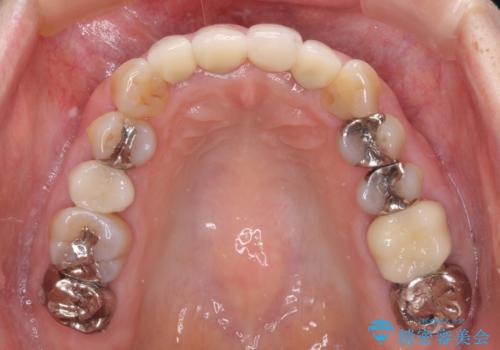

1. 折れてしまった前歯 インプラントによる補綴治療の治療前

3. 折れてしまった前歯 インプラントによる補綴治療の治療後